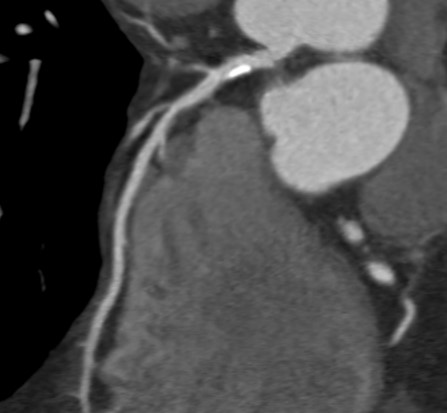

Weiterhin können erste Veränderungen mit diagnostischen Früherkennungsmethoden wie moderner Bildgebung erkannt werden (Abb. 3). Hier ist wissenschaftlich insbesondere das mittels Scores festgestellte mittlere Risiko im mittleren Alter eine prädestinierte Gruppe von gesundheitsorientierten Menschen. Bei niedrigem Risiko bleibt eine weitere Früherkennung weniger effektiv, da meist keine relevanten Befunde provoziert wurden. Ein höheres Risiko ist bereits sehr hoch und lässt keine wesentlichen therapierelevanten weiteren Erkenntnisse durch weitergehende Diagnostik erwarten.

Abb. 3. (Bildmaterial der EPC GmbH – European Prevention Center). Dargestellt ist ein Kalkplaque am Abgang der vorderen absteigenden Herzkranzarterie in einer Herz-Computertomographie (CT) eines 56-jährigen Check-Up-Individuums ohne jegliche Symptomatik.